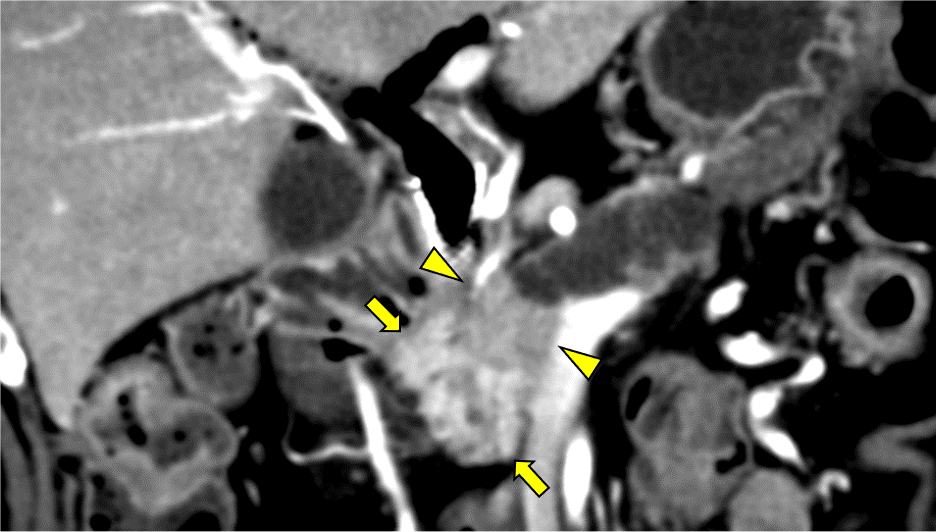

図1.造影CT 膵実質相 Coronal像 70keV

膵体尾部で主膵管の拡張と膵実質の萎縮(矢印)あり。主膵管は膵頭部で途絶しており、主膵管の途絶部には膵実質相で低吸収の膵癌病変(矢頭)を認める。

図2.造影CT 膵実質相 Coronal像 40keV

40keVの仮想単色X線画像では70keVの画像と比較して、膵癌病変(矢頭)と正常膵実質(矢印)のコントラストはより明瞭に描出されている。